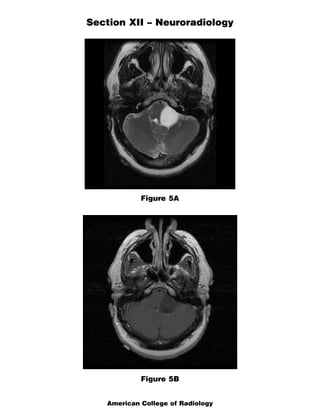

The document discusses several radiology cases involving the brain and spine. Question 291 presents CT scans of a woman with headaches and asks for the most likely diagnosis of a fat-containing extraconal orbital mass. Question 292 shows MR images of a woman with extremity weakness and asks for the most likely diagnosis of multiple brain and spine lesions. Question 293 presents MR images of a man with back pain and asks for the diagnosis of a posterior spinal mass seen on the images.